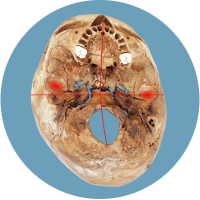

Das größte Problem besteht darin, dass der Kopf in seiner Struktur verändert wird – die Schädelbasis wird schief. Davon sind hauptsächlich die Stellung der Ohren (Gleichgewichtsorgane), die Kiefergelenke (Zahnfehlstellungen) und Halswirbelkörper betroffen. Kritisch wird dies spätestens, wenn sich die Kinder zum Ende des 1. Lebensjahres aufrichten und eine schiefe Wirbelsäulenhaltung entwickeln.

Die verschobene Position der Gleichgewichtsorgane ist durch die roten Kreuze gekennzeichnet.

Fehlerhafte Informationen aus den verschobenen Gleichgewichtsorganen bzw. dem Nackenrezeptorenfeld beeinflussen die Verarbeitung im Gehirn und können zu einer Fehlhaltung der Wirbelsäule führen.

Dadurch wird der Kopf intuitiv schief gehalten, der Körpersinn entwickelt sich nicht richtig, was Auswirkungen auf die motorische Entwicklung und Körperwahrnehmung nach sich zieht.

Stimmt die Passung der obersten Wirbel nicht, kann dies zu einer Verkrümmung der Wirbelsäule führen.